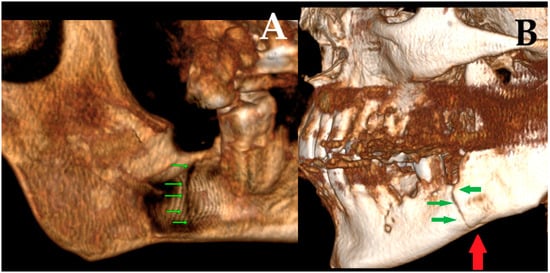

Figure 5. Mandibular fractures occurring after cyst enucleation are uncommon but clinically significant complications, typically associated with extensive cortical thinning and compromised bone integrity. In the present case, a postoperative vertical fracture was detected on tomographic reconstruction ((A) green arrows indicating the fracture line in lingual aspect), demonstrating a clear fracture line. The fracture was non-displaced, and the continuity of the cortical margins was preserved, allowing conservative management with intermaxillary fixation using elastics. At the one-month follow-up, a repeat tomographic reconstruction revealed progressive bone healing ((B) red arrow shows the healed contour line, trabecular continuity, and stable alignment; green arrows indicate the vertical fracture line and demonstrate progressive osseous healing) of the mandibular border, confirming satisfactory consolidation under elastic guidance. Similar iatrogenic or delayed pathological fractures have been reported in cases involving large cystic lesions or deeply impacted third molars, where chronic expansion leads to progressive cortical attenuation [1,2]. In such scenarios, even minor masticatory forces may precipitate a fracture during the postoperative period. Prophylactic reinforcement with miniplates has therefore been proposed for large or high-risk lesions to prevent pathological fractures [9,10]. Finite element analyses have further demonstrated that rigid internal fixation can restore mandibular stiffness and reduce stress concentrations along weakened borders [4]. More recently, patient-specific titanium plates have been introduced as customized reinforcement tools in extensive cystic or tumor-related defects, enabling optimal adaptation and minimizing postoperative morbidity [3]. Although the fracture in this case healed uneventfully through conservative management, the radiological evidence of significant cortical thinning and the presence of an impacted third molar adjacent to the lesion underscores the potential value of prophylactic plating in comparable cases.